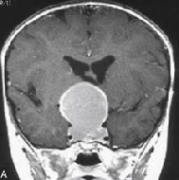

颅咽管瘤是由鞍区或鞍上区Rathke囊的残余细胞形成的肿瘤,具有囊性和实型成分。虽然它们是良性的,WHO为I级,但由于该病难以治愈,使得它们的生长行为...

颅咽管瘤占儿童脑肿瘤的 5% 到 15%,成人占 1%。脑垂体区域容易发生颅咽管瘤,可能影响内分泌功能。此外,它们靠近视神经和视交叉可能会导致视力问题...

颅咽管瘤手术治疗有多种手术入路,入路的选择应根据肿瘤的大小、生长部位、肿瘤的钙化程度、接近脑脊液通路的便利程度来决定。小杰的主刀医生INC巴...

颅咽管瘤能治好吗?颅咽管瘤是儿童常见的颅内肿瘤,占儿童颅内肿瘤的5.6%~15%,占儿童鞍区肿瘤的54%。组织学分类为WHO I级肿瘤,根治性切除是优选治疗。...

颅咽管瘤是一种神经上皮来源的肿瘤,起源于沿原始颅咽管路径的鳞状细胞。其发病率在每10万人年0.5至2.5之间,不因性别或种族而异。颅咽管瘤占全部颅...